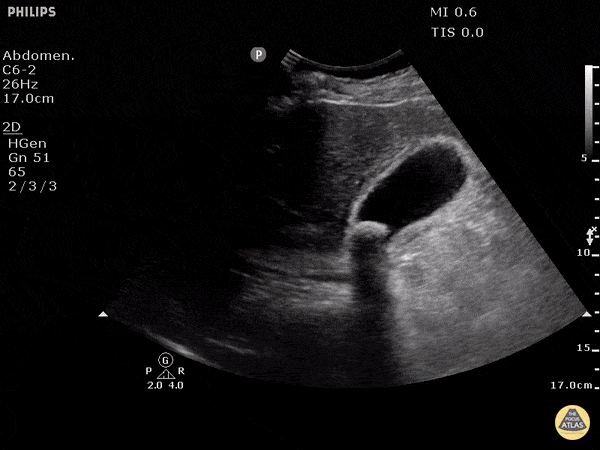

This clearly demonstrates a stone in the gallbladder neck as a hyperechoic structure with posterior shadowing. The neck is not always clearly visualized on first glance so it is important to scan through the gallbladder in two planes to exclude stones in the neck. Other signs of acute cholecystitis include pericholecystic fluid, gallbladder wall thickening (>3mm) common bile duct dilatation, and positive sonographic Murphy's sign. Justin Bowra MBBS, FACEM, CCPU Emergency Physician, RNSH et al. (Mo)